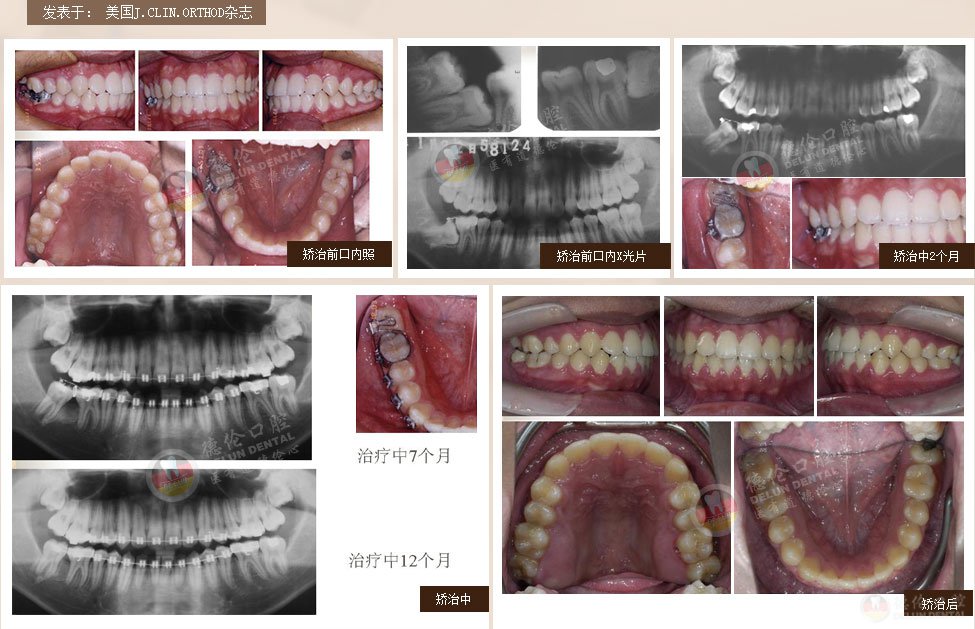

案例1:男 17岁

牙齿症状:下颌右侧第二、第三磨牙水平阻生,下颌左侧第三磨牙水平阻生

矫治方法:下颌拔除两颗第三磨牙(智慧齿)

案例2:女 24岁

牙齿症状:牙列不齐、下颌第二、第三磨牙水平阻生,左侧磨牙锁牙合

矫治方法:拔除上颌及右下第一双尖牙,左下第二双尖牙以及2个下第三磨牙